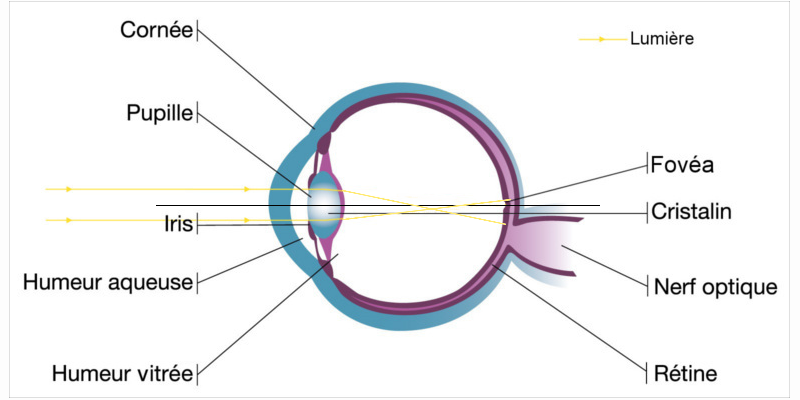

L’œil est composé de deux organes qui sont responsables de la réfraction de la lumière, c'est-à-dire responsables de notre bonne vision, à savoir la cornée et le cristallin.

Ces deux parties de l’œil sont censées être sphériques pour que la puissance soit la même partout. Cependant cela reste théorique car dans la pratique la puissance de l’œil est rarement la même partout et il se peut que le rayon de courbure soit plus important dans certaines partie de l’œil.

Si l’œil a une légère déformation au niveau de la cornée ou du cristallin, cela va engendrer ce que l’on appelle un cylindre, et c’est pour cela que les patients atteints d’astigmatisme ont besoin d'un cylindre avec un axe dans leur correction pour corriger ce défaut.